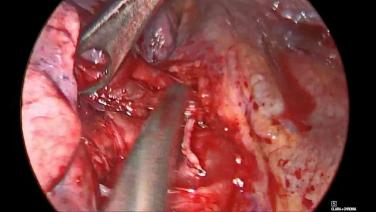

VATS Lobectomy Using HARMONIC™ 1100 Shears, ECHELON FLEX™ Powered Vascular Stapler, and SURGICEL™ Absorbable Hemostat